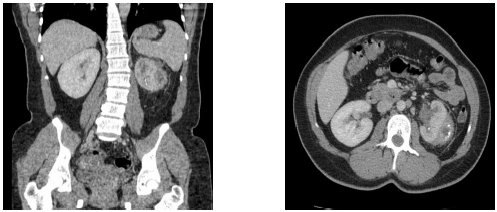

Jovem de 20 anos estava hígido até duas semanas atrás, quando começou a apresentar desconforto torácico e fraqueza de membros. Ao exame: PA = 120/90mmHg; FC = 75bpm; FR = 24irpm; temperatura axilar = 36,3ºC. Exame cardiovascular sem alterações, mas com estertores crepitantes nos 1/3 inferiores de ambos os pulmões. No hemograma: hematócrito = 30,7%; hemoglobina = 10,4g/dL; plaquetas = 345mil/µL; leucograma = 14.500/µL; ureia = 214mg/dL; creatinina = 30mg/dL; potássio = 5,5mEq/L; sódio = 141mEq/L; cálcio = 7,6mg/dL; fósforo = 7,3mg/dL; magnésio = 3,0mg/dL; proteína total = 5,1g/dL (albumina 2,1g/dL); AST = 18ui/L; ALT = 14ui/L com EAS apresentando 3+ de proteína. Os complementos séricos estavam normais e os seguintes exames foram negativos: HBsAG, antiHCV, FAN e ANCA. Iniciado procedimento de hemodiálise, no 4º dia de hospitalização, apresentou hemoptise volumosa com instabilidade hemodinâmica. Foi para o centro de terapia intensiva e realizou tomografia computadorizada de tórax (conforme imagem a seguir). A dosagem do anticorpo antimembrana basal glomerular foi de 257EU/mL (valor de referência: < 5EU/mL).

O diagnóstico mais provável é: